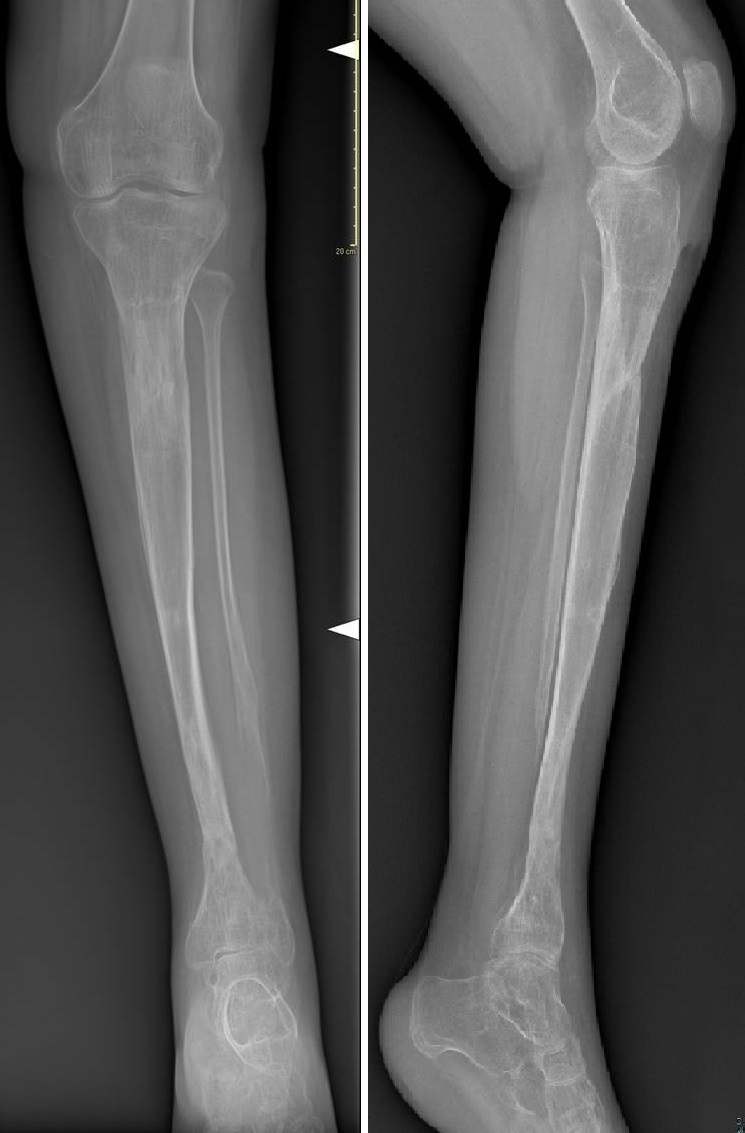

1) L'inchiodamento endomidollare (chiodi di Rush o Kirschner o telescopici) dopo accurata pulizia chirurgica dei monconi di pseudoartrosi e del periostio limitrofo, viene aperto il canale midolalre mediante perforatori per garantire adeguato apporto ematico sui monconi quindi si ottiene la stabilizzazione della lesione con un infibulo endomidollare di lunghezza e calibro adeguato alle dimensioni della tibia per favorire la consolidazione si aggiungono adiuvanti biologici come innesti ossei prelevati dalla stessa cresta iliaca del paziente e/o concentrato di mesenchimali prelevato dalla cresta iliaca (MSC); nel caso dei chiodi di Rush o Kirschner l'infibulo è inserito dal basso attraverso il calcagno, attraversa l'articolazione tibio-tarsica per dare sufficiente stabilità, e consente di posizionare il piede in leggera supinazione per prevenire la deformità in valgo pronazione tipica della patologia. Tali chiodi richiedono la sostituzione periodica ( 2-3 anni) per crescita del paziente.

Quando le condizioni lo consentono si possono utilizzare chiodi telescopici che hanno il vantaggio di ridurre l'accorciamento definitivo della tibia a fine crescita e di essere sostituiti meno frequentemente, perché consentono di allungarsi (entro certi limiti) durante la crescita in lunghezza della tibia del paziente.